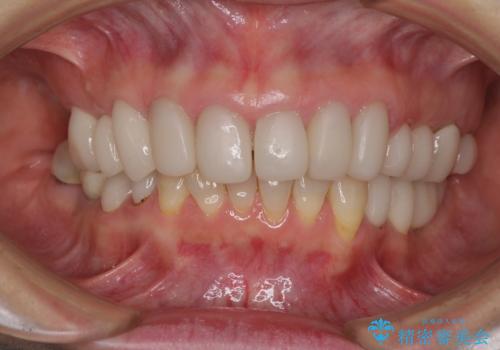

歯の欠損を放置 オールセラミックブリッジによる補綴治療

下顎には抜歯が必要な歯があったため、抜歯後に治癒を待ち、上顎とともにオールセラミックブリッジにて補綴治療を行うこととしました。

治療開始の日に欠損部も含めて仮歯が装着され、今までの不具合や不快感があっという間に改善されました。

抜歯部位の治癒を待つために時間がかかりましたが、来院回数は数回で済み、患者様には大変満足していただきました。